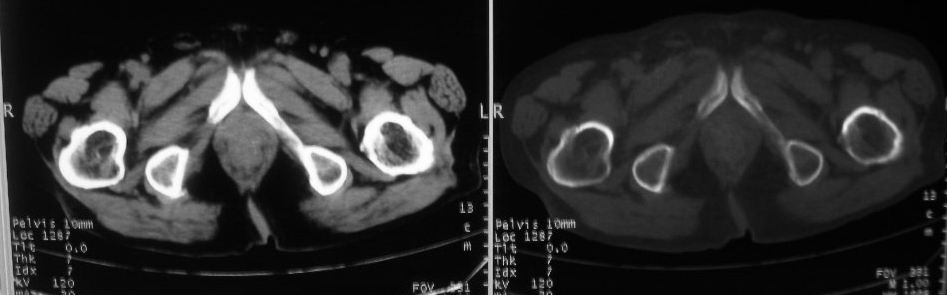

以下是引用zjzjr在2008-10-3 12:59:00的发言:[br]前列腺癌伴左髂骨\\腰椎转移可能性大.

以下是引用卜一在2008-10-3 13:40:00的发言:[br]前列腺癌!左髂骨\\腰椎转移?建议行全身骨扫描!

以下是引用深泽交通医院在2008-10-3 15:33:00的发言:[br]前列腺实性增大伴分叶状,与包膜间隙境界不清;椎体松质区间结节样密度影,考虑:前列腺癌,并椎体成骨性转移